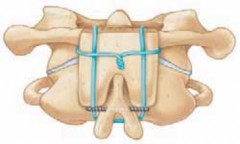

4. Each iliac crest graft is cut into a trapezoid-like shape (one end is narrower than the other) so that they can be wedged between the C1 and C2 posterior arches (

TECH FIG 5A

5. The grafts are snugly wedged into place. The wires are then tightened around the grafts, twisted, and cut (

TECH FIG 5B

TECH FIG 5•

Brooks arthrodesis.

A.

Lateral view demonstrating a wedge-shaped graft between the spinous processes to prevent hyperex-tension. The graft is shaped so that one end is narrower than the other to achieve a good fit.

B.

The grafts are snugly wedged between the C1 and C2 posterior arches, and the wires are tightened around the grafts.